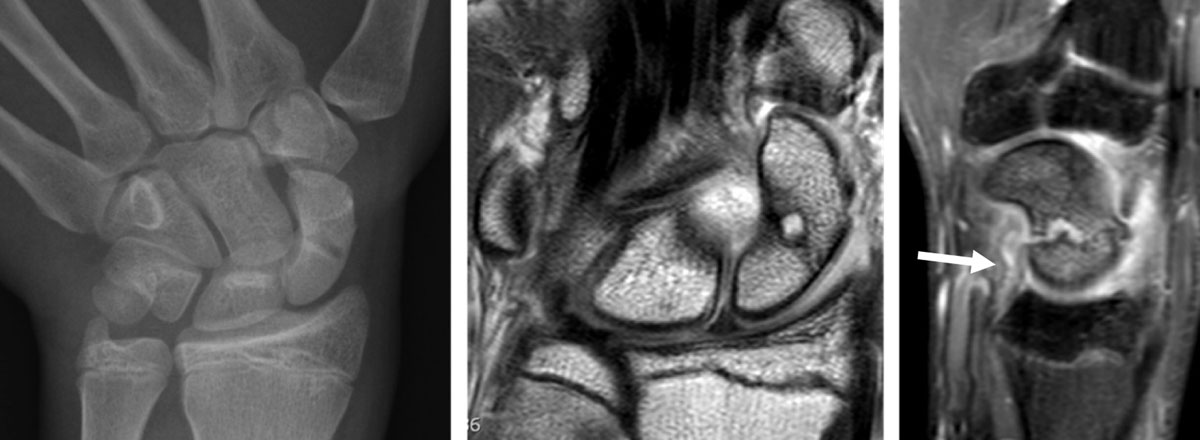

Figure 3

Evolution of scaphoid fracture with pseudarthrosis in a 17-year-old male. Radiograph obtained in AP view with ulnar deviation (a) one month after trauma discloses an evident fracture of the scaphoid middle third (which was not visible on the first radiographs performed on the day of trauma). As the wrist remaining painful and bone scintigraphy performed one year after trauma was positive at the level of the scaphoid, MRI was obtained to exclude an avascular necrosis at the proximal pole of the scaphoid. Coronal proton-density slice (b) and sagittal fat saturated proton-density slice (c) revealed pseudarthrosis without osteonecrosis and an extensive bone marrow edema of the whole scaphoid with surrounding soft tissue edema and elongation of the palmar RSC ligament (arrow) on c.